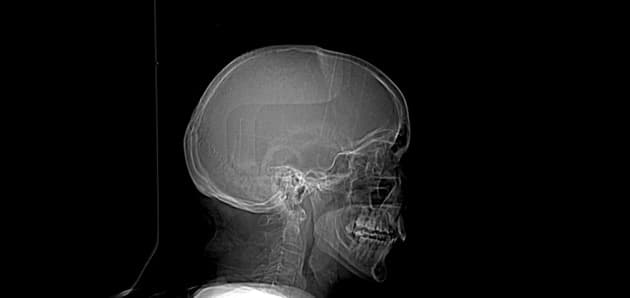

Ngộ độc methanol cấp tính

Mù đột ngột, nhức đầu và ngất đột ngột

- Có hoại tử vùng vỏ đồi (putamen) hai bên, đối xứng, cấp tính, không xuất huyết, với hạn chế khuếch tán (restricted diffusion) và giảm độ khuếch tán trung bình trên bản đồ ADC tương ứng.

- Không có ngấm thuốc (enhancement) bất thường sau tiêm thuốc cản quang.

- Ngoài ra, có hạn chế khuếch tán (restricted diffusion) ở vùng vỏ trán hai bên.

- Các điểm âm tính quan trọng bao gồm: dây thần kinh thị giác (optic nerves), đường dẫn truyền thị giác (optic pathway), thùy chẩm (occipital lobes), chất trắng dưới vỏ và chất trắng sâu, và hai bán cầu tiểu não (cerebellar hemispheres) đều bình thường.

- Chụp cộng hưởng từ sọ não (MRI brain) về cơ bản không có bất thường khác.

Bệnh nhân này được chẩn đoán ngộ độc methanol cấp tính (acute methanol poisoning) dựa trên hình ảnh học và được xác nhận bằng xét nghiệm sinh hóa.

Chẩn đoán

Ngộ độc methanol cấp tính (acute methanol poisoning)